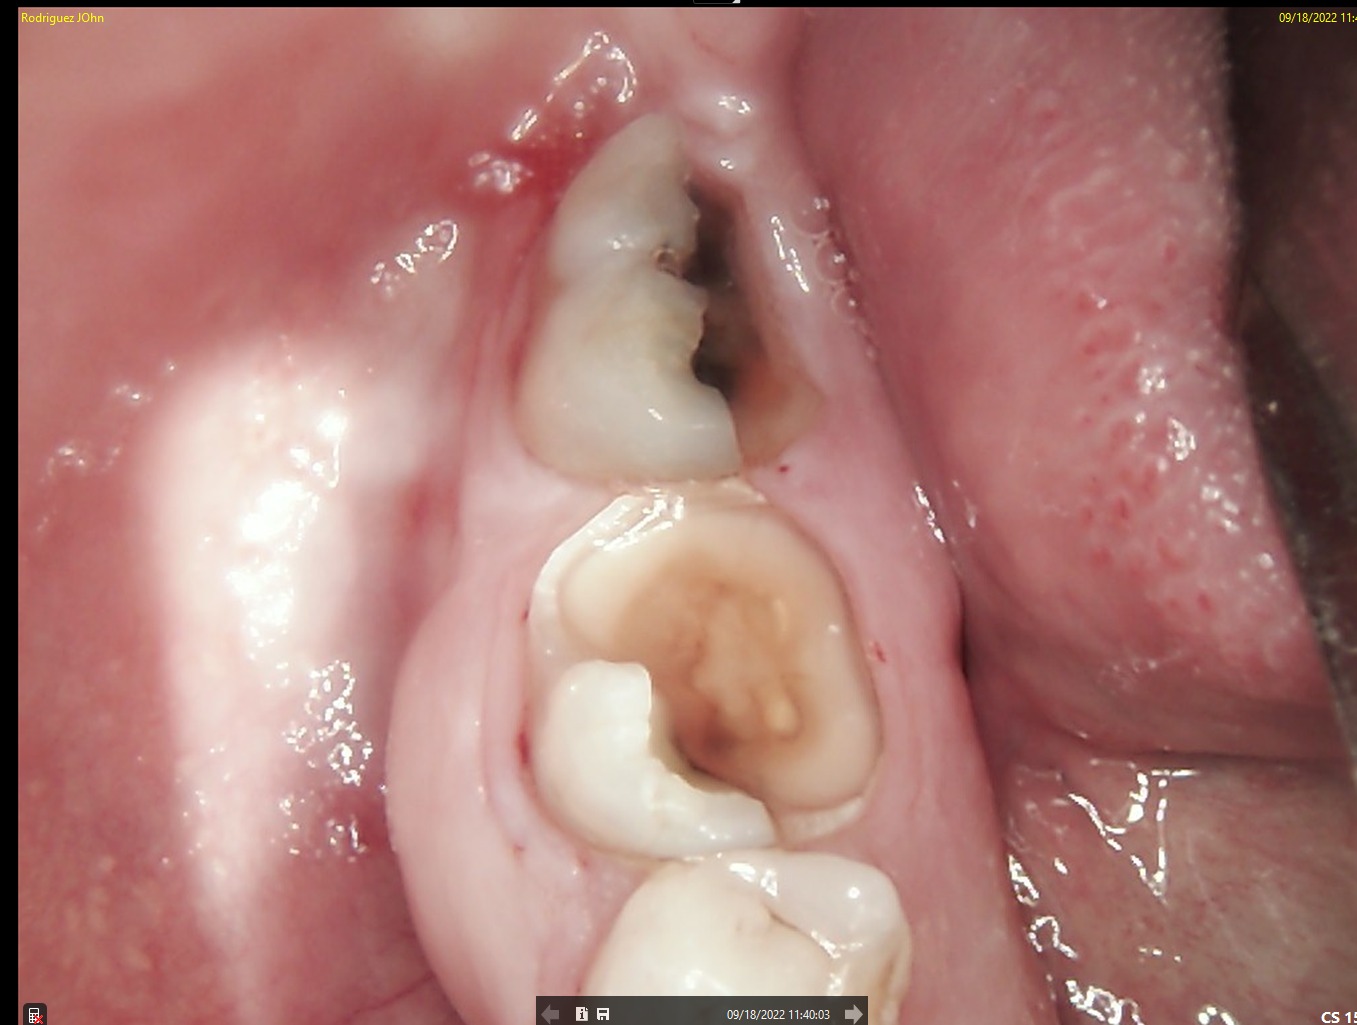

A patient presented with functional impairment and partial tooth loss in the posterior mandible. The main complaints included reduced chewing efficiency, and the need for a long-term, biologically stable restoration.

INITIAL STATE

CBCT imaging was used for precise implant planning, including evaluation of bone volume and anatomical landmarks. Digital planning allowed optimal implant positioning to ensure long-term stability and prosthetic-driven placement. Intraoral and periapical images confirmed the clinical condition prior to surgical intervention.